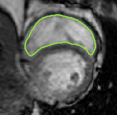

4.2 Visual assessment

We select the case that achieves the highest and lowest dice score for visual assessment. Fig. 4 shows example segmentation results where the proposed method achieved the highest agreement with the ground truth delineations. Fig. 5 shows example segmentation results where the proposed method achieved the lowest agreement with the ground truth delineations.